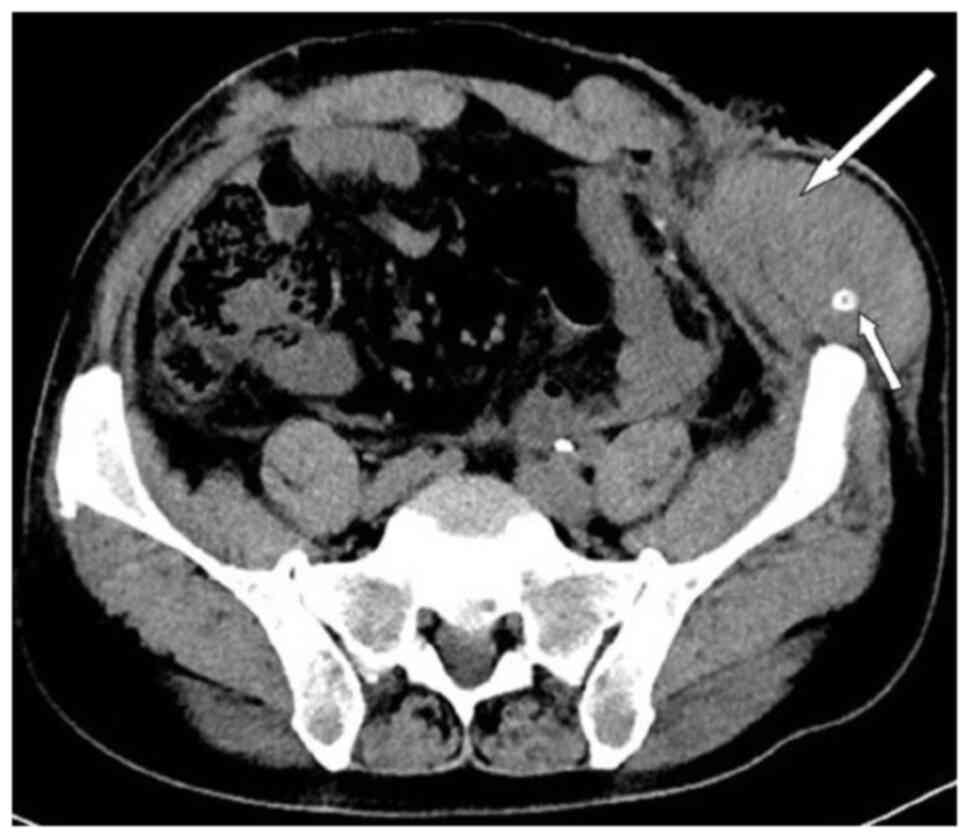

Subsequently, the patient presented with a lump around the colostomy stoma site and intermittent abdominal pain in November 2020. Physical examination revealed a lump measuring ~10×10 cm around the stoma, which did not reduce in size when the patient was lying flat. Abdominal CT (Fig. 4) revealed that the intestinal tube had protruded into the subcutaneous fat layer of the abdomen. Based on the patient's medical history, physical examination (a lump around the colostomy stoma site) and the result of abdominal CT (Fig. 4), a parastomal hernia was suspected. Surgery was the recommended treatment. Routine preoperative blood tests, coagulation function, and liver and kidney functions showed no abnormalities. Parastomal hernia repair surgery was performed using the keyhole technique in November 2020. A relatively soft drainage tube was placed subcutaneously in the surgical area. The patient recovered well after the surgery and was discharged on the third postoperative day without removing the drainage tube. During discharge, the surgical area was not compressed. However, five days after discharge, the patient experienced swelling, pain and bleeding at the surgical site. Abdominal CT showed a hematoma in the surgical area (Fig. 5). After taking hemostatic treatment measures (hemostatic drugs, compression hemostasis), fresh blood still slowly flowed out from the drainage tube. Dynamic reexamination of coagulation function showed that it gradually deteriorated, and the activated partial thromboplastin time was gradually delayed to 60 sec, which was 20 sec longer than normal (reference range, 20–40 sec). The patient had stubborn anemia, and after multiple blood transfusions, no significant increase was identified in hemoglobin, which remained between 45–68 g/l (normal range, 130–175 g/l). A bone marrow biopsy was also performed to investigate the cause of persistent bleeding (Fig. 6). The bone marrow smear was stained using the Wright staining method and 200 cells were counted under a microscope. The results showed abnormal proliferation of plasma cell lines in bone marrow smears, accounting for 35% of total cells, with an immature plasma cell composition accounting for 21.0% of total cells (normal range, 0–0.8%). This result is consistent with the diagnosis of multiple myeloma (10,11). Fig. 6 shows the characteristics of abnormal plasma cells: This type of cell was significantly different in size, with the cell body and nucleus appearing circular, elliptical, ovoid or irregular in shape. The nucleus was misaligned, the chromatin of the nucleus appeared as a granular or loose network and certain cells showed obvious nucleoli. The cytoplasm was rich, stained opaque dark blue and flame-like, with obvious light staining bands around the nucleus. Nodular protrusions and vacuoles were easily observed, while no particles were seen. The morphological features were consistent with those of MM (10). Further testing revealed elevated serum immunoglobulin A (IgA) levels of 76.7 g/l (normal range, 0.82–4.53 g/l) and significantly increased serum β2 microglobulin (β2-microglobulin) levels of 16,205 ng/ml (normal range, 604–2,286 ng/ml). Based on the results of the bone marrow puncture, the bone destruction, anemia and bleeding were attributed to MM. After consultation with a hematologist, the patient was diagnosed with MM (IgA-λ type, Durie-Salmon Stage III). The Durie-Salmon staging system is a classic staging system for MM. The staging criteria for Stage III are as follows: One or more of the following abnormalities must be present: Hemoglobin <8.5 g/dl; serum calcium >12 mg/dl; very high myeloma protein production; IgG peak >7 g/dl; IgA peak >5 g/dl; Bence Jones protein >12 g/24 h; and >3 lytic lesions on bone survey (11). The patient was transferred to the hematology department and was treated with the PCD regimen (bortezomib, cyclophosphamide, dexamethasone), chemotherapy and blood transfusion. The specific dosage of medication is calculated based on the patient's body surface area. One chemotherapy cycle is 4 weeks and this patient received 6 cycles of chemotherapy. Afterwards, the patient received maintenance treatment with bortezomib monotherapy. The seventh rib lesion invaded the surrounding soft tissue, and the interventional department performed an empty needle puncture biopsy on it. The pathological and immunohistochemical results of the puncture tissue are consistent with multiple myeloma (10). The lesion was determined to be plasmacytoma, suggesting involvement of MM (Fig. 7), and the immunohistochemical results were as follows: CD138 (+), CD38 (+), cytokeratin (CK) (−), Ki67 (15%, +), Lambda (+) and MM oncogene 1 (+) (Fig. 8). CK negativity indicated the absence of malignant cells of epithelial origin. The patient's condition gradually improved, with increasing hemoglobin levels, recovering coagulation function, absorption of the hematoma around the stoma (Fig. 9) and alleviation of bone pain. For the past 2 years, the patient has been regularly treated in the hematology department and the progression of the MM has been slow (Figs. 10 and 11). Fig. 10 is a PET/CT image of the patient diagnosed with MM one year later. The arrows in Fig. 10 indicate the metabolic status of the lesionsin the right seventh posterior rib, upper sternum, and first lumbar spine. The increased metabolism of these three main lesions is consistent with the manifestation of MM. In Fig. 11, row A represents the situation of lesion in the upper sternum at different time-points; row B shows the situation of lesion in the upper sternum at different time-points; and row C shows the situation of lesion in the upper sternum at different time-points. The arrows in Fig. 11Aa, Ba and Ca refer to the lesions of the upper sternum, the seventh rib on the right side and the first lumbar vertebra when MM was diagnosed. Fig. 11Ab-Cb shows the respective lesions 1 year after the diagnosis of MM and Fig. 11Ac-Cc shows them at 2 years after the diagnosis of MM. After comparison, the progression of these three lesions was not obvious. After treatment, the soft tissue mass around the lesion of the right seventh rib gradually became smaller. The patient has not experienced any worsening bone pain symptoms since being diagnosed with MM. The patient has been regularly visiting the hematology outpatient department. During the follow-up period, the patient's blood routine, coagulation function and serum immunoglobulin are being tested every two months, and chest CT and spinal CT examinations conducted every 6 months. During follow-up, there has been occasional mild anemia but no coagulation abnormalities.

Figure 4.

Periostomy hernia. Abdominal computed tomography indicated a visible intestinal canal protruding into the subcutaneous fat layer (arrows).